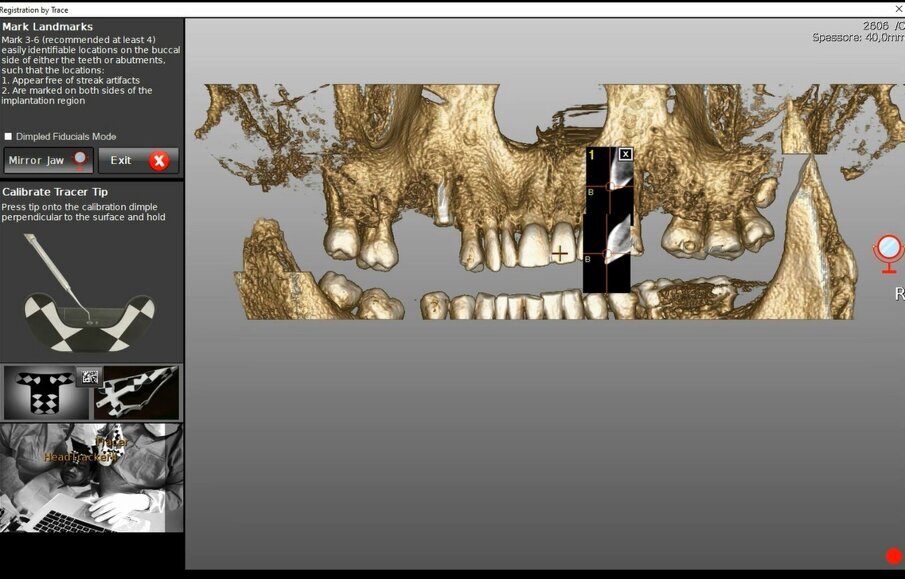

La registrazione (matching) è sempre necessaria, sia nella chirurgia guidata sia in quella navigata ma le differenze tra le due tecnologie sono già ravvisabili nell’uso che fanno di questo complesso algoritmo matematico. Nella chirurgia guidata la registrazione avviene su una media delle superfici TAC e STL del modello ed ha il compito di posizionare il modello (digitale o digitalizzato) rispetto alla TAC e, dunque, rispetto al piano di trattamento: l’errore di questo posizionamento corrisponde ad un dislocamento complessivo degli impianti durante la realizzazione clinica. Un processo protocollato, meccanizzato ed automatizzato permetterebbe di misurare questo errore e prevederlo per ciascun caso. È esperienza diffusa di ogni odontoiatra, però, che la realtà clinica, sebbene digitalizzata e protocollata, non è automatizzata; questa esperienza esita nella produzione di dispositivi la cui validità clinica non è costante ma rientra in un range che prevede, purtroppo, anche l’inaccettabilità. Nel caso della chirurgia guidata purtroppo vengono a coincidere due fattori concettualmente deleteri: l’impossibilità di verificare l’accettabilità del manufatto se non ad intervento ultimato e l’assoluta impossibilità di ripetizione della procedura chirurgica perché il fallimento spesso si associa a perdita di osso. Ciò si verifica anche in un protocollo full digital sebbene con minore frequenza e dipende dalle condizioni di lavoro assolutamente non standardizzabili. Una dima può nascondere un errore non clinicamente valutabile ma significativo. La chirurgia navigata fa uso allo stesso modo della registrazione ma esclusivamente a scopo diagnostico ed in fase di pianificazione (Figg. 3a, 3b). A scopo interventistico la chirurgia navigata richiede un’altra registrazione che si verifica in tempo reale e che ha lo scopo di posizionare i dati TAC nella realtà clinica di intervento integrandoli in un sistema di realtà aumentata on-demand (Fig. 4). Per ottenere questa sovrapposizione in tempo reale è necessaria una superficie di riferimento comune tra TAC e realtà clinica. Unica sul mercato la tecnologia navigata Navident® by Claronav® mette a disposizione ben 5 protocolli diversi per ottenere questo risultato coprendo tutto l’ampio ventaglio di realtà cliniche che ci si può ritrovare ad affrontare (pazienti totalmente edentuli, pazienti parzialmente edentuli, pazienti parzialmente edentuli ma con importanti fenomeni di scattering e beam hardening, etc.) (Figg. 5a-5f).

Figg. 3a, 3b - La registrazione di un modello con ceratura diagnostica nel software Navident® by Claronav®. a) Identificazione di punti di accoppiamento; b) integrazione finale del modello con ceratura diagnostica nel software per la pianificazione. N.B. Questo uso dell’algoritmo di registrazione è esclusivamente diagnostico in una tecnica di chirurgia navigata.